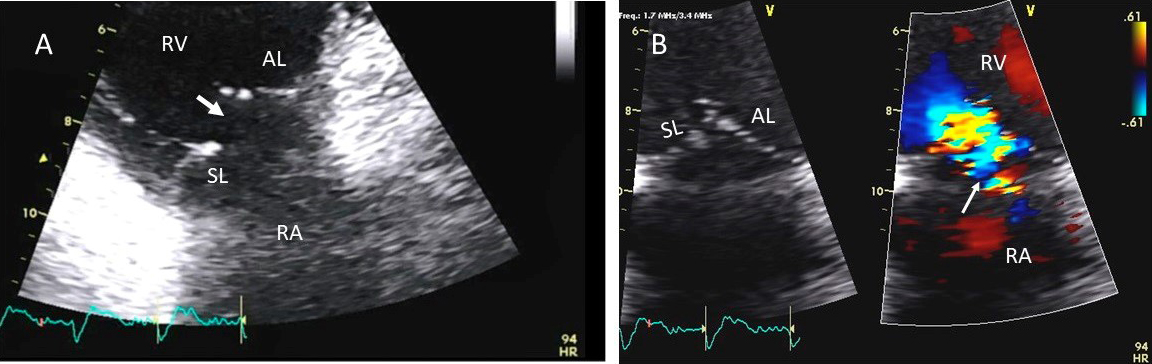

Examples of valvular injury directly from implantable cardioverter-defibrillator lead placement (Fig. 5A–C) or a permanent pacemaker (Fig. 6A–C) or endomyocardial biopsy in cardiac transplant recipients (Fig. 7A,B) are shown.

Fig. 7.Tricuspid regurgitation following endomyocardial biopsy. (A) Flail tricuspid valve leaflet that occurred as a complication of an endomyocardial biopsy. Apical 4 chamber view showed flail septal leaflet (SL, septal leaflet; AL, anterior leaflet). (B) Color-flow Doppler imaging. Eccentric, anteriorly directed jet of tricuspid regurgitation (SL, septal leaflet of tricuspid valve; AL, anterior leaflet of tricuspid valve).